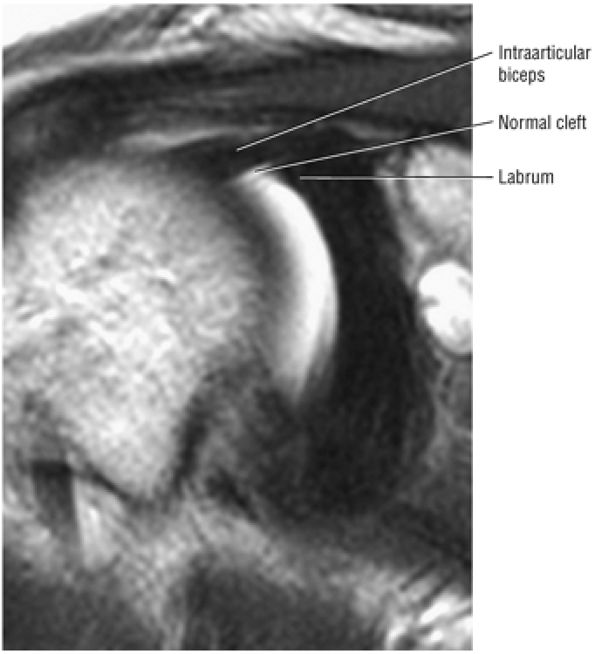

The BLC is classified as type 1, 2, or 3.

Type 1 BLC has the superior labrum firmly attached to the superior pole of the glenoid.

The superior labral sulcus in BLC types 2 and 3 should not be mistaken for the more anterior (anterosuperior quadrant) sublabral foramen (also known as the sublabral hole).

Type 1 BLC (see Fig. 8.74A; Fig. 8.75): The BLC is firmly adherent to the superior pole of the glenoid. There is no sublabral foramen in the anterosuperior quadrant. This type of BLC attachment corresponds to the morphology of the BLC in the posterior wedge or type B labrum.